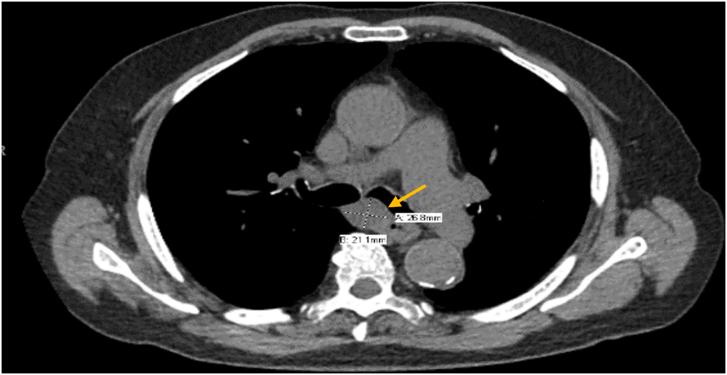

Adenoid cystic carcinoma (ACC) is a malignant epithelial tumor that predominantly originates in the salivary glands of the head and neck. However, ACC arising in the thoracic cavity is a rare entity. Diagnosis of primary esophageal ACC (EACC) involves use of gastrointestinal endoscopic ultrasound fine-needle aspiration; however a low diagnostic yield has been reported in the literature. We describe an uncommon presentation of EACC debuting with predominant airway obstructive symptoms and diagnosed through endobronchial ultrasound-guided fine-needle aspiration. We propose the use of an endobronchial sonographic approach to diagnose EACC and other esophageal malignant neoplasms with mediastinal involvement and airway proximity.

摘要

腺样囊性癌(ACC)是一种主要起源于头颈部唾液腺的恶性上皮性肿瘤。然而,发生在胸腔的ACC是一种罕见的实体。原发性食管腺样囊性癌(EACC)的诊断涉及使用胃肠内镜超声细针穿刺;然而,文献报道其诊断率较低。我们描述了一例罕见的EACC表现,以主要的气道阻塞症状首发,并通过支气管内超声引导下细针穿刺确诊。我们建议使用支气管内超声检查方法来诊断EACC以及其他累及纵隔和靠近气道的食管恶性肿瘤。